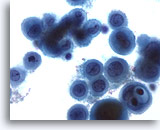

Peritoneal effusion: Metastatic carcinoma of the breast. Note cells with targetoid intracytoplasmic vacuoles containing mucin droplets. 40X

Metastatic carcinoma of the breast. Note cells with targetoid intracytoplasmic vacuoles containing mucin droplets.

40X